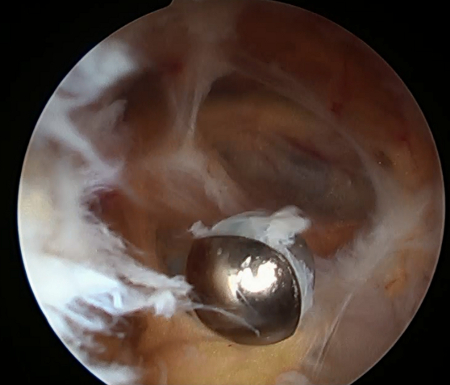

Knee pathologies such as trauma, arthritis, or infection may result in increased synovial fluid volume and pressure.[17][18] Effusions develop when the absorption of synovial fluid lags behind microvascular filtration. Intra-articular pressure increases significantly during knee extension, and this may explain why pain occurs most often in this position. Although many reports have suggested an inherent weakness in the posterior capsule, no data support this.[Figure caption and citation for the preceding image starts]: Synovitis within cystFrom the collection of Dr John D. Kelly IV; used with permission [Citation ends].